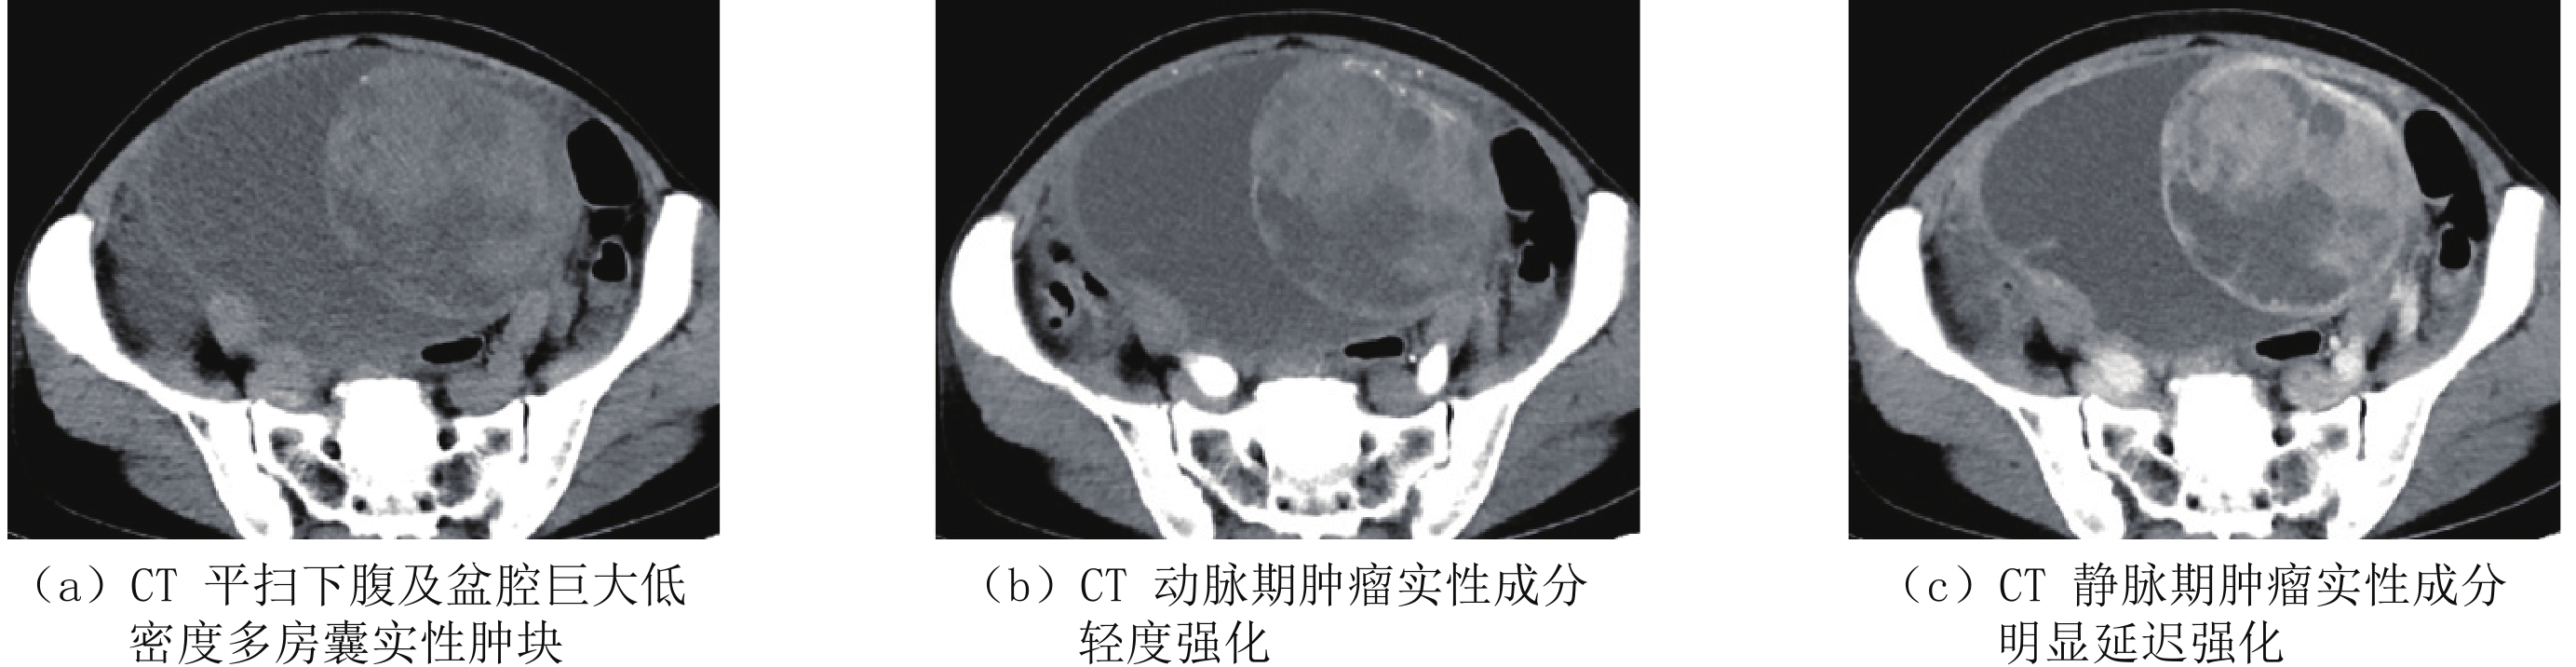

表 1 血清CA125、HE4在卵巢上皮良、恶性肿瘤组中阳性率的比较Table 1. Comparison among positive rates of serum CA125 and HE4 in benign and malignant ovarian epithelial tumors分组 CA125 HE4 恶性肿瘤组(n=84) 85.71%(72/84) 80.95%(68/84) 良性肿瘤组(n=72) 38.89%(28/72) 22.22%(16/72) χ${} ^2$ 36.94 53.81 P 0.000 0.000 CT、血清CA125、HE4单独及联合应用对卵巢上皮恶性肿瘤的诊断结果比较显示CA125诊断的灵敏度高于HE4,HE4诊断特异度高于CA125,CA125联合HE4诊断的准确率高于CT;CT+CA125+HE4诊断准确率高于单独CT或肿瘤标志物诊断(表2),部分病例CT图像见图2~图5。

CT技术的发展有利于显示恶性肿瘤病变本身及继发改变的细节,从而及时诊断和准确分期[15-16]。总结本组资料并复习相关文献,我们认为卵巢上皮性恶性肿瘤的CT一般具有下述特征[4,17-18]:早期主要表现为囊性或囊实性,病情发展呈囊实性或部分实性;体积较大,一般直径大于4 cm;呈多房囊腔,肿瘤囊壁及囊腔内分隔厚薄不均匀,最大可超过3 cm;增强瘤体实性部分较明显强化,囊内可见明显强化的壁结节;后期往往伴有腹、盆腔积液及周边结构侵犯、淋巴结及远处转移,有时可见到较明显的肿瘤血管及两侧卵巢同时发病。

本组CT诊断准确率为82.12%,对大部分Ⅱ期肿瘤和全部 Ⅲ、Ⅳ 期肿瘤均得以正确诊断及分期。漏诊者均为单发体积较小的Ⅰ、Ⅱ期囊性肿瘤,因为体积较小、实性成分少且强化不明显而误认为良性囊腺瘤;3例良性肿瘤因为体积较大且实性成分强化较明显而误诊为恶性。因此CT不能单独根据病灶大小、强化程度等对病灶性质进行判断。此外卵巢转移瘤和原发性肿瘤有时具有相似的CT表现,而肿瘤标志物CA125及HE4则可以一定程度上弥补CT的不足。